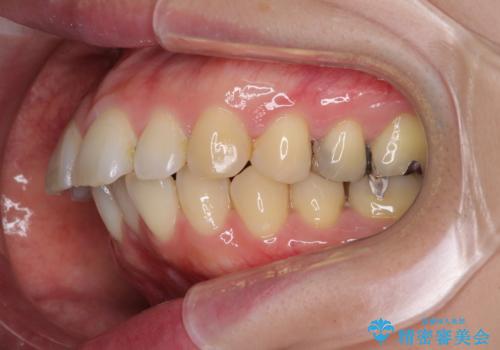

- クリアブラケット

- 口が閉じずらく、口元が突出している状態でした。

上下左右の歯を1本ずつ、合計4本抜歯して、ワイヤーにて矯正することとなりました。

もともと下の前歯の永久歯が1本欠損しており、抜歯部位の選択を考慮しなければならない症例でした。シミュレーションを事前に行い、下顎の抜歯部位を決定しました。